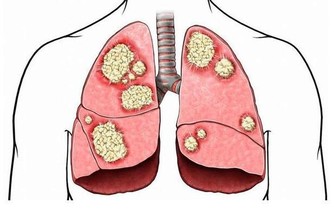

♥ 人不是老死的,不是病死的,是氣死的

《黃帝內經》講得很清楚:“怒傷肝,喜傷心,悲傷肺,憂思傷脾,驚恐傷腎,百病皆生於氣。”